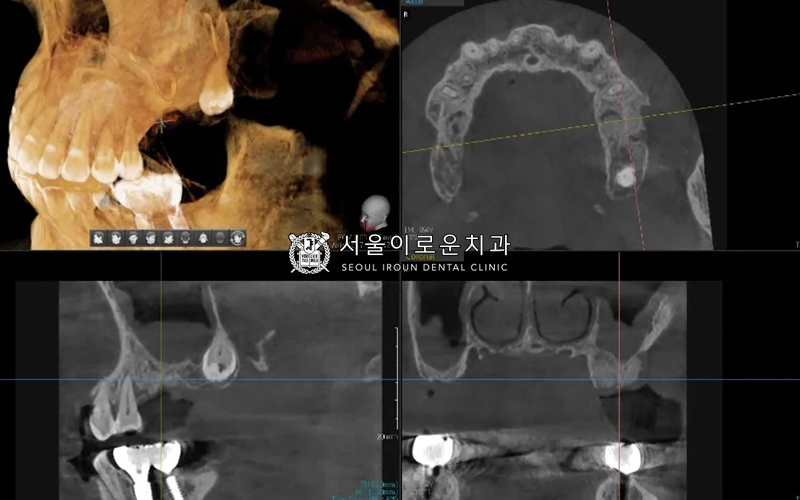

바로 다음 치료계획인

오른쪽 위 임플란트 (#16,17)

치료에 들어갔는데요~!

앞서 말씀드린 고난도 임플란트

‘상악동 거상술’을 진행하였습니다!

환.자분의 경우,

발치된지 오래되고

심한 치주염으로 잇몸뼈가

다수 부족하였으나

남아있는 뼈의 높이가 3mm 이상으로

‘치조정 접근법’으로

상악동 거상술을 통해

뼈이식 후 임플란트 동시 식립을

진행하였습니다!

치료마무리 사진입니다 🙂

오른쪽 위는 고난도 임플란트인

상악동 거상술을 진행한 뒤

안정적으로 식립되어있는 것을

관찰할 수 있습니다 🙂

왼쪽 위 역시 뼈이식이 잘되었는데요.

bone이 안정적으로 확보되기까지

조금 더 기다린 뒤 임플란트를

식립하기로 결정하였습니다 🙂